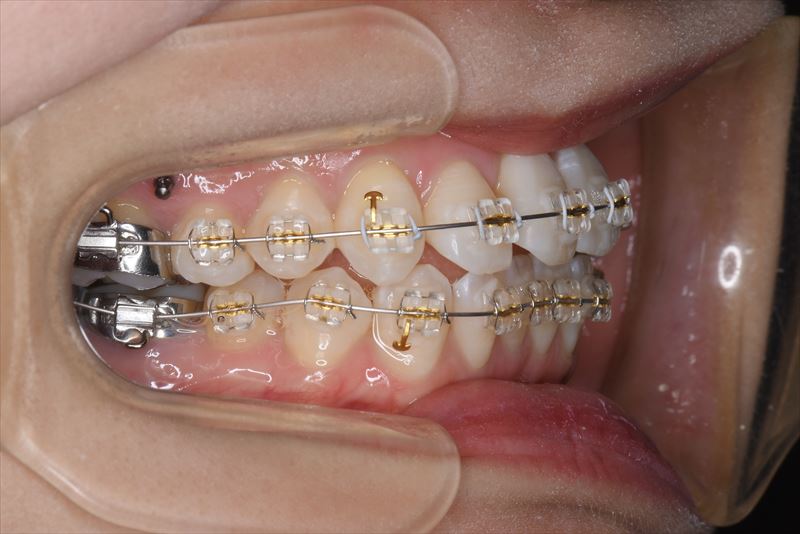

治療中